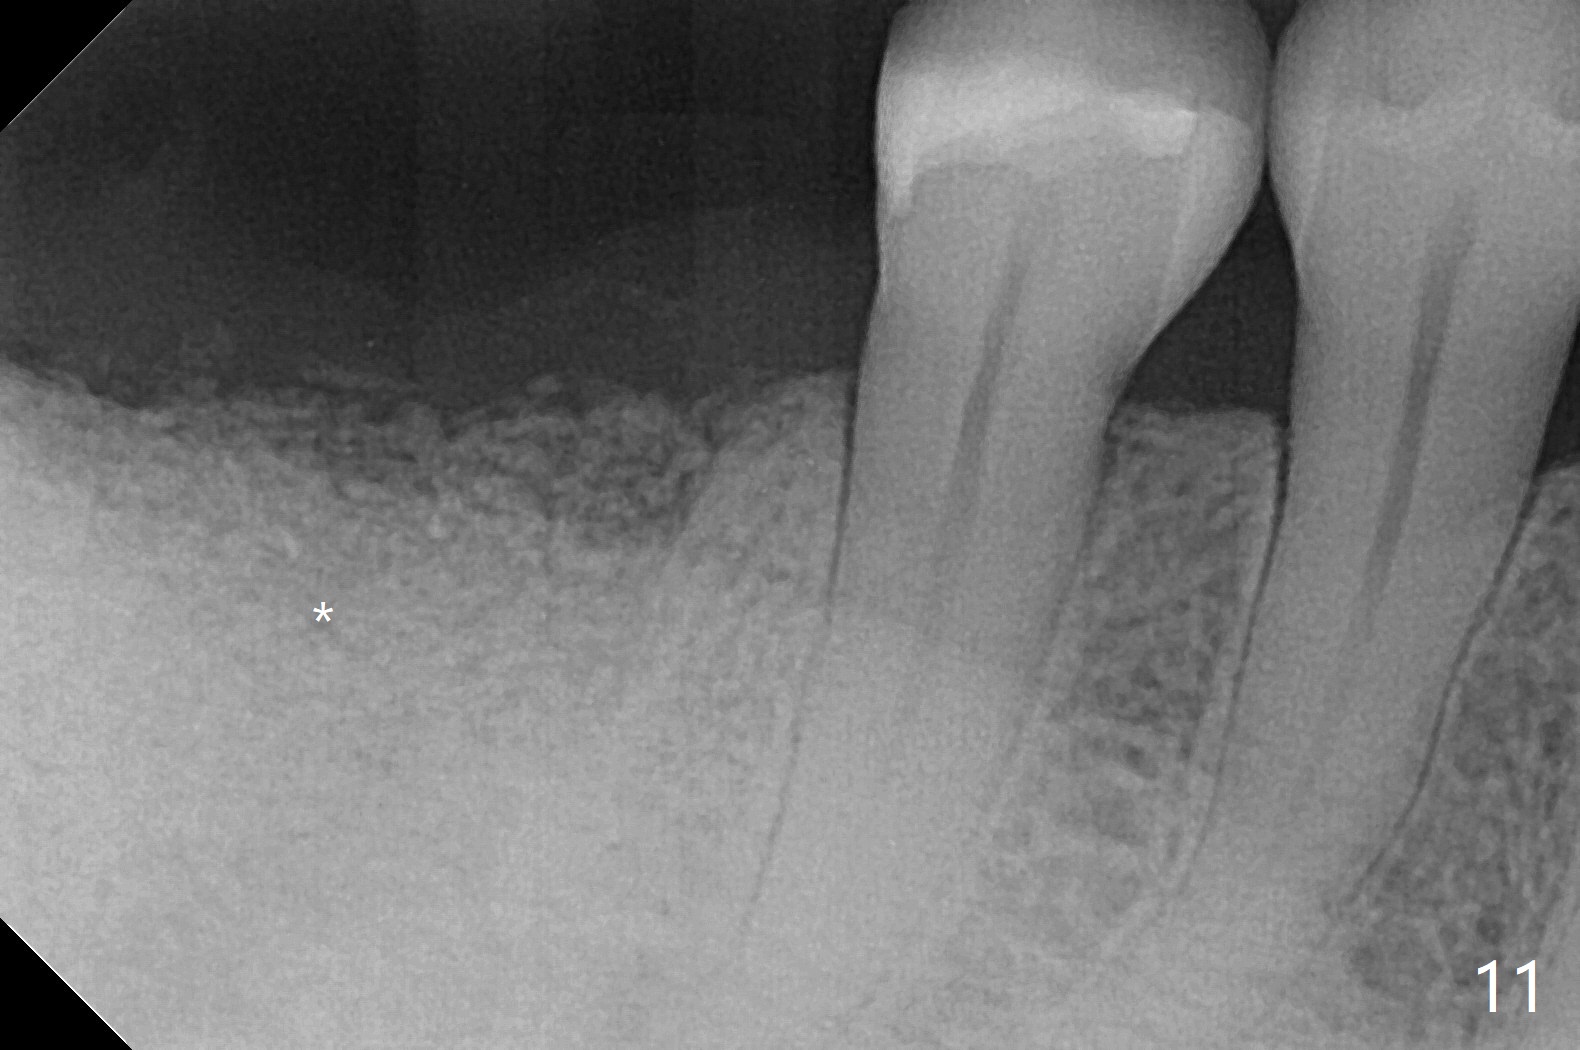

There are signs of periimplantitis at #30 eleven months postop (Fig.1 (* bone loss)). The bony defect (Fig.2) will be filled with allograft mixed PRF liquid to form sticky bone (Fig.3,4), followed by PRF membrane (not shown) and a piece of 6-month membrane (Fig.5). A hole is cut so that the 6-month membrane can slide down the abutment (Fig.2,5 A) to cover the bone graft around the implant (Fig.2,7 I). Setting acrylic is applied around the abutment and neighboring teeth for further protection and holding (Fig.8). The periimplantitis does not resolve nearly 7 months post graft. The implant will be removed. Prepare UF extra wide kit and try to insert 6.5 or 7.0 mm tap. Also prepare sticky bone and Cytoplast for wound closure. Implant removal involves surgical handpiece, 6.2/7 mm trephine bur, elevators, and implant driver. The defect is large (Fig.9) with the low buccal crest (Fig.10) and bone graft with PRF ("sticky bone") is placed, covered by PRF and 6-months membrane (Fig.11). The next implant will be placed with guide. If oral hygiene is not ideal, choose a bone level implant. The middle of the wound dehiscences slightly 8 days postop (Fig.12), accounting for mild loss of bone graft 1 year postop (Fig.14). The keratinized gingiva is apparently wide 1 year postop (Fig.13). There is mild loss of bone graft in the middle of the superficial area (Fig.14). The buccal plate seems to regenerate 1 year postop (pandemic delay, Fig.15).